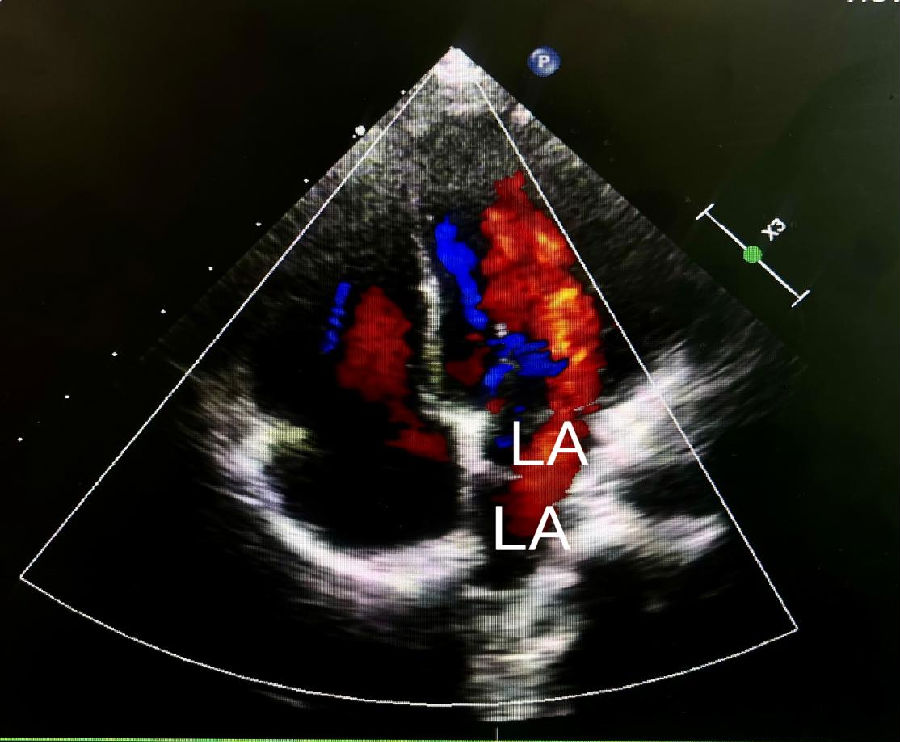

在体检中,有时可以通过听诊检测到心脏杂音。杂音的强度取决于血流通过隔膜的速度。超声心动图(经胸或经食道)是评估三房心解剖学和生理学的主要成像方式,彩色多普勒下的花色血流信号通常表示血流的加速和湍流的出现,这表明可以通过血流通过隔膜时可能有梗阻。经食管超声心动图的成像优于经胸超声心动图,可以明确的诊断三房心,并区分真正的左心房、左心房附属物以及隔膜的形态和梗阻程度。三维超声心动图是一种新的诊断工具,可以给临床提供额外的信息,能够明确隔膜的大小、位置和开口数量等。